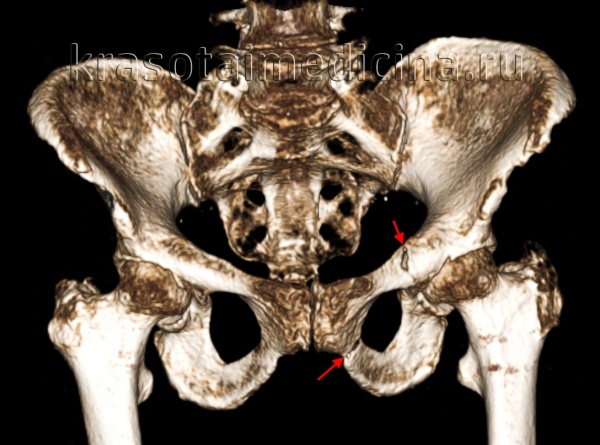

- Компьютерная томография.